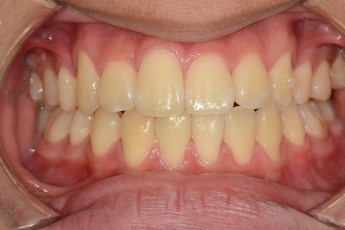

BEFORE & AFTER